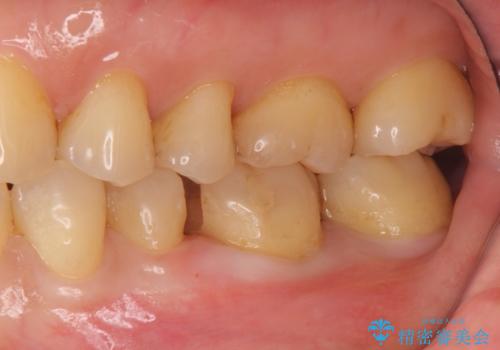

目立つ銀歯を全て白く セラミックで虫歯治療

- 銀の詰め物が気になるとのことで来院。

2本隣り合っているつめものを、同時にやりかえをしました。

向かい合う銀歯を同時にやり変えることで、コンタクト(歯と歯の間の形)を理想的に仕上げることができ、ものも挟まりにくいように仕上げることができます。